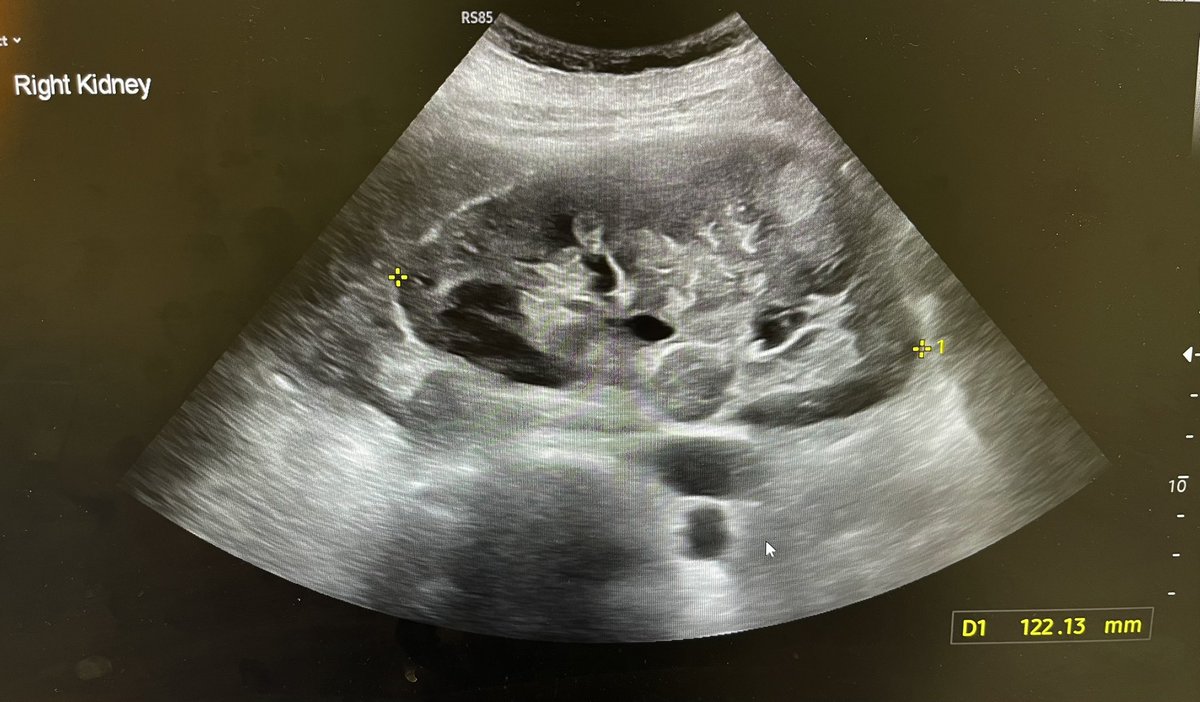

Cortical scarring. @Rad_Munagi